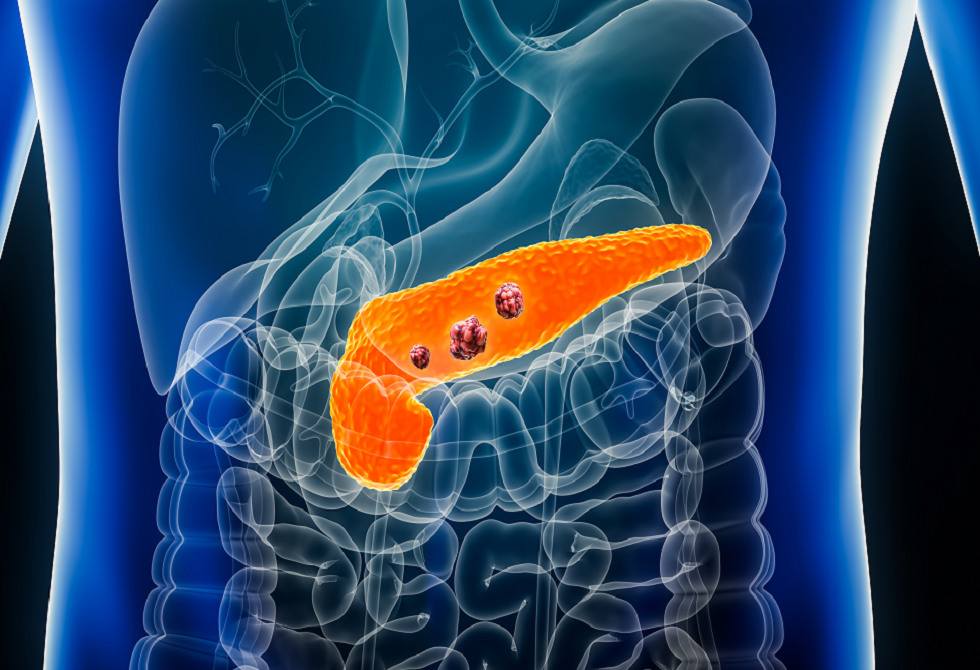

فحص دم جديد قد ينقذ آلاف الأرواح من سرطان البنكرياس

طور علماء من جامعة بنسلفانيا وعيادة مايو فحص دم مبتكر يمكن أن يساعد في الكشف المبكر عن سرطان البنكرياس، أحد أخطر أنواع السرطان وأصعبها علاجا.

ويعتمد الفحص الجديد على دمج أربعة مؤشرات حيوية في اختبار واحد: المؤشرين المعروفين CA19-9 وTHBS2، والبروتينين الجديدين ANPEP وPIGR، اللذين وُجدت مستوياتهما أعلى لدى المصابين بسرطان البنكرياس في مراحله المبكرة مقارنة بالمتطوعين الأصحاء.

وعند دمج المؤشرات الأربعة، بلغ معدل دقة التشخيص 92%، مع نتائج إيجابية خاطئة بنسبة 5% فقط لدى الأشخاص غير المصابين، وكشف نحو 8% من الحالات في مراحل مبكرة للمرض.

ويأمل الباحثون أن يُستخدم الاختبار لفحص الأشخاص الأكثر عرضة للإصابة، مثل من لديهم تاريخ عائلي للمرض أو عوامل وراثية أو تكيسات في البنكرياس أو التهاب البنكرياس المزمن.

ويشير الدكتور كينيث زاريت، الباحث الرئيسي في الدراسة، إلى أن إضافة المؤشرين الجديدين حسّنت بشكل ملحوظ قدرة الاختبار على كشف السرطان مبكرا، كما ساعدت في التمييز بين السرطان والحالات غير السرطانية مثل التهاب البنكرياس، وهو ما كان يمثل تحديا للاختبارات السابقة.

ورغم النتائج المبشرة، يحتاج الاختبار إلى سنوات من التجارب قبل اعتماده للاستخدام العام.

وفي الوقت الحالي، يظل سرطان البنكرياس مرضا صعب العلاج وغير قابل للشفاء غالبا، إذ يؤدي إلى فشل الأعضاء نتيجة غزو الأعضاء المجاورة وانسداد القنوات الصفراوية والمعوية، وانتشار السرطان عبر الدم والجهاز اللمفاوي.

ويؤدي سرطان البنكرياس أيضا إلى اضطراب إفراز هرمونات البنكرياس مثل الأنسولين والغلوكاغون، ما قد يسبب مشاكل في مستويات السكر بالدم. وتشمل الأعراض الشائعة للمرض اليرقان وفقدان الشهية والوزن والتعب والغثيان أو القيء والإسهال أو الإمساك.

وأشارت دراسة سابقة إلى أن أكثر من نصف المرضى المصابين بالأنواع الأقل قابلية للشفاء من السرطان، بما في ذلك سرطان البنكرياس، يتوفون خلال عام من التشخيص.

وفي سياق متصل، نجح فريق بحثي إسباني مؤخرا في تطوير خطة علاجية "ثلاثية الفعالية" قلصت حجم خلايا سرطان البنكرياس، ما يمنح الأمل في تحسين نتائج العلاج مستقبلا.

نشرت الدراسة في المجلة الطبية AACR.